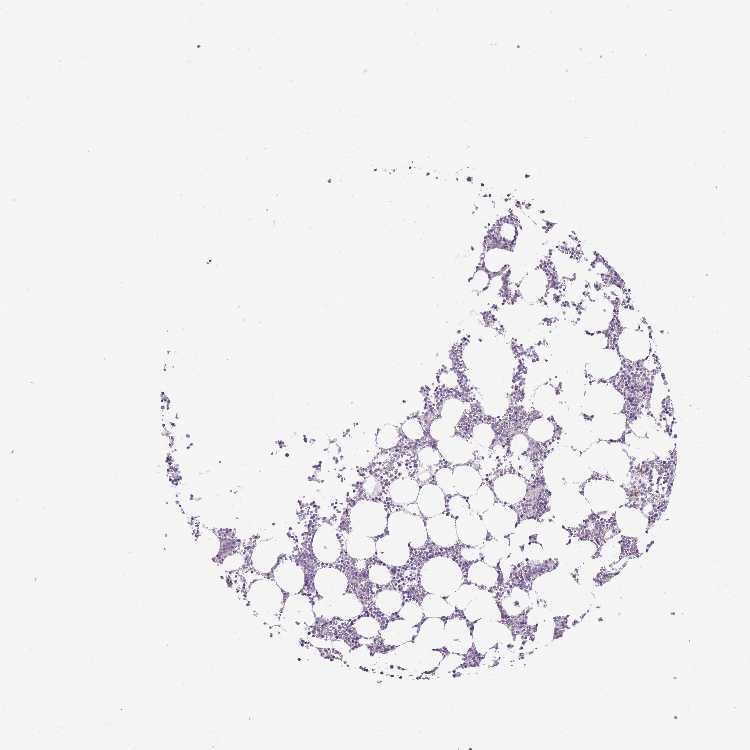

BONE MARROW - Antibody stainingi

Antibody staining in the annotated cell types in the current human tissue is reported as not detected, low, medium, or high, based on conventional immunohistochemistry profiling in selected tissues. This score is based on the combination of the staining intensity and fraction of stained cells.

Each image is clickable and will lead to virtual microscopy that enables deeper exploration of all samples and also displays staining intensity scores, fraction scores and subcellular localization as well as patient and tissue information for each sample.

Antibody HPA042632Antibody HPA048484

Hematopoietic cells Not detectedNot detected